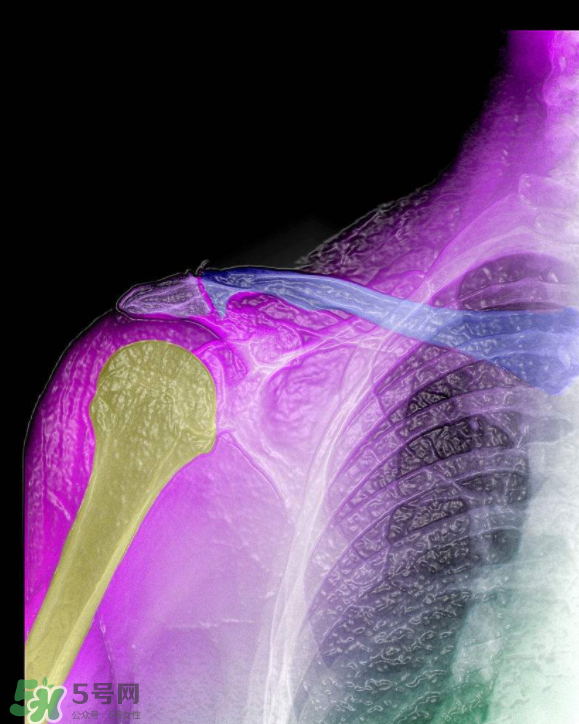

骨刺是怎么形成的?骨刺怎么治療?

骨刺是一種比較發(fā)作起來會讓人很難受的病,很多人不清楚骨刺到底是什么樣的,下面5號網(wǎng)的小編為你們介紹骨刺是怎么形成的?骨刺怎么治療?

骨刺是怎么形成的

1、骨刺,多發(fā)于活動度最大、負(fù)重最多的頸椎、腰椎、骶椎、膝關(guān)節(jié)、足跟等部位。隨著年齡的增長,人的關(guān)節(jié)軟骨彈性會銳減,軟骨膠原纖維顯露,關(guān)節(jié)中部活動時(shí)極易磨損,其外周軟骨面便代謝性增殞肥厚,最后骨化形成骨刺。職業(yè)性持久用力、長期被迫體位不良、慢性或機(jī)械性刺激、跌打損傷等是誘發(fā)骨刺形成的原因。

2、骨刺患者一旦增生的骨刺刺激鄰近組織和壓迫神經(jīng)根時(shí),就會出現(xiàn)局部或放射性骨刺的疼痛。主要表現(xiàn)為上肢麻痹、肩背疼痛、頸項(xiàng)僵硬、頭暈、胸悶不舒、心悸心慌、坐骨神經(jīng)痛、下肢麻痹痛、怕冷、膝關(guān)節(jié)腫痛、上下樓梯困難、不能下蹲等一系列骨刺的病理變化。如不及時(shí)治療,就會使骨刺的病情加重,增加治療難度。因此,這些都是骨刺形成的原因。